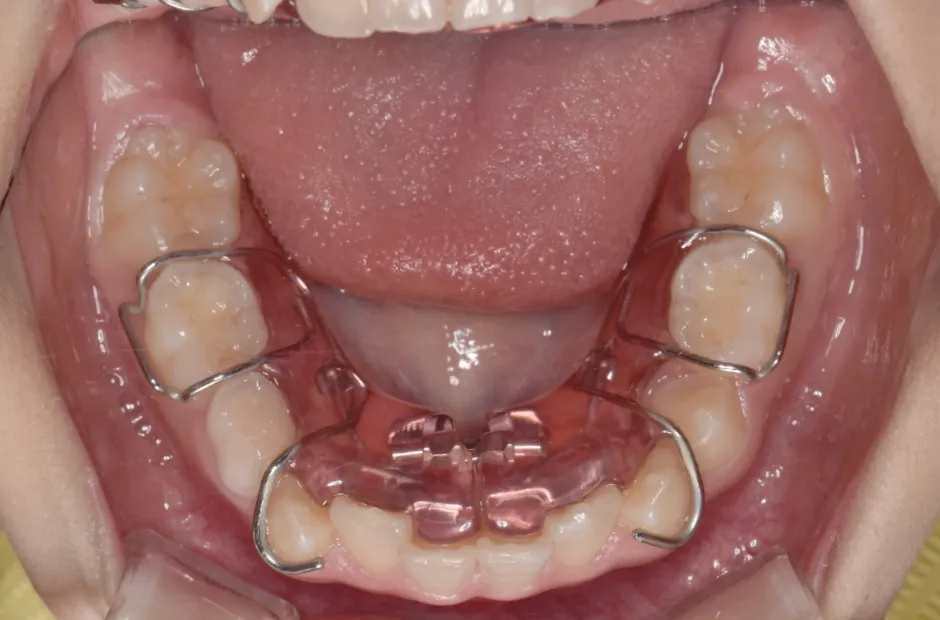

反対咬合

| 診断名・主訴 | 前歯反対咬合 |

|---|---|

| 年齢・性別 | 12歳・男性 |

| 治療期間・回数 | 1年半 18回 |

| 治療に用いた主な装置 | リンガルアーチ(前方誘導弾線) |

| 抜歯部位 | なし |

| 治療費 | 35万円(税抜) |

| リスク・副作用 | 装置による違和感・疼痛・歯肉退縮・歯根吸収・虫歯のリスクなど |